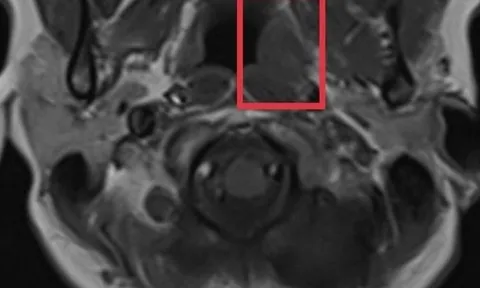

Cẩn trọng với loại ung thư nguy hiểm nhưng có triệu chứng mơ hồ

Nữ bệnh nhân 44 tuổi bỗng thấy đau đầu nhiều, kéo dài khoảng 1 tháng, càng về sau cơn đau càng dữ dội kèm theo chóng mặt.